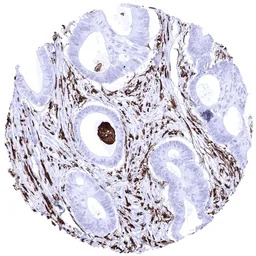

IHC-P analysis of human HLA AR negative colorectal adenocarcinoma tissue section using GTX04429 HLA-DRA antibody [MSVA-470R] HistoMAX.

HLA DR negative colorectal adenocarcinoma showing strong HLA DR positivity of capillaries and tumor associated inflammatory cells.